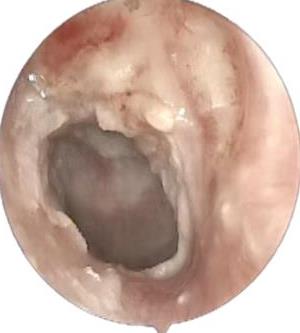

• 医用生物蛋白胶应用于耳内镜下鼓膜修补术的临床疗效

摘要:目的 分析医用生物蛋白胶应用于耳内镜下鼓膜修补术的临床疗效。方法 回顾性分析2022年10月-2023年10月该院收治的60例单纯鼓膜穿孔患者的临床资料,根据手术方法不同,将患者分为研究组和对照组,各30例。研究组术中使用医用生物蛋白胶粘合残余鼓膜和修补材料;对照组术中采用明胶海绵覆盖修补鼓膜。观察两组患者术后的鼓膜愈合情况(鼓膜愈合率、愈合时间、干耳时间和外耳道上下径)和并发症发生情况;于手术前后,采用纯音测听法(500、1 000、2 000、4 000 Hz),测量两组患者气导阈值,观察听力改善程度;采用视觉模拟评分法(VAS)评分,评估患者术后疼痛程度。结果 两组患者术后鼓膜愈合率、愈合时间、外耳道上下径和并发症发生率比较,差异均无统计学意义(P > 0.05)。研究组术后平均气导听阈明显低于对照组,差异有统计学意义(P < 0.05)。研究组术后干耳时间短于对照组,术后第1天疼痛VAS评分明显低于对照组,差异均有统计学意义(P < 0.05)。结论 医用生物蛋白胶应用于耳内镜下鼓膜修补术,可有效地降低气导听阈,缩短干耳时间,减轻患者疼痛,且不增加并发症发生率,值得临床推广应用。